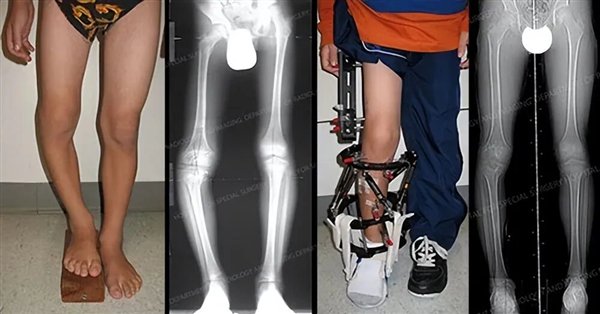

简单来说,就是先敲断骨头,然后体外安装一种牵引设备,反方向两边拉伸,来刺激骨头再次生长,最终通过骨头的延长来增加身高,所以也叫肢体延长术。

在过去,只有腿部有问题(例如畸形和长短腿)影响正常生活的人,才会冒险选择这样的治疗方式,而如今,却成了人们改变外观的一种手段。

腿部畸形矫正案例